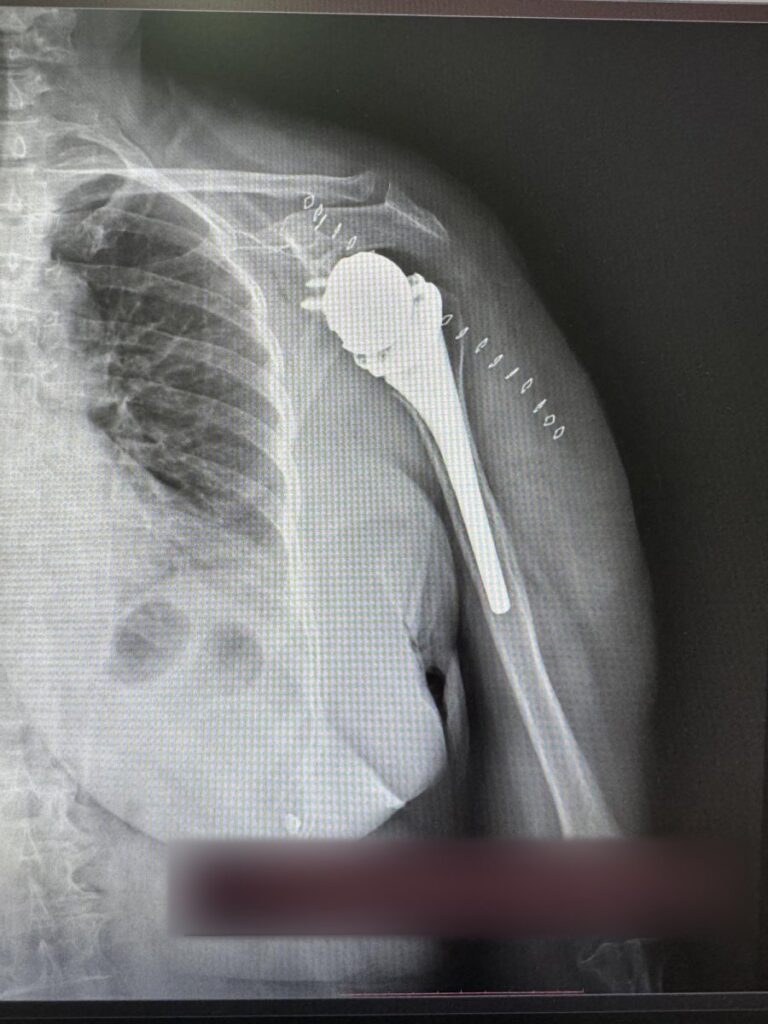

Për herë të parë në Klinikën e Ortopedisë të Qendrës Klinike dhe Universitare të Kosovës janë kryer dy operacione për vendosjen e protezave të supit.

SHSKUK-ja ka njoftuar se ekipi mjekësor në përbërje të dy ortopedëve, si dhe ekipit nga Klinika e Anesteziologjisë dhe stafit infermieror, me sukses të plotë kanë kryer këto dy operacione ortopedike.

“QKUK-ja kishte përfituar si donacion tavolinën operative për ndërhyrje në krahë nga Klinika me renome botërore ‘Schulthess Klinik’, Zvicër”, thuhet në njoftim.